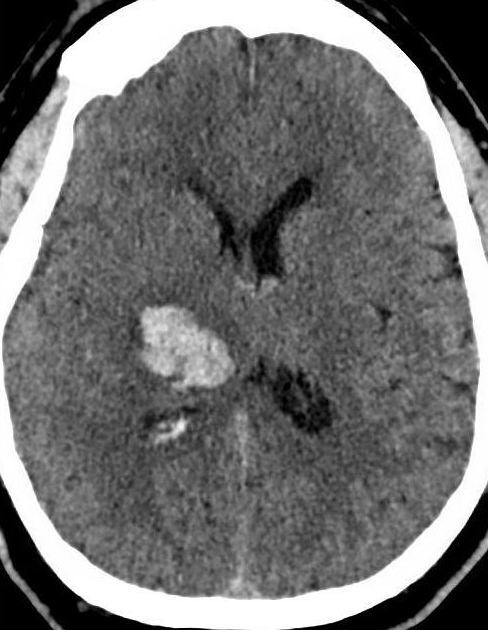

Let’s say a patient presents with typical stroke symptoms – sudden onset of left-sided weakness (hemiplegia) and sensory loss. How do you tell if it’s due to an ischemic or hemorrhagic stroke? The difference is important, as one is treated with blood pressure control while the other may receive tPA and more liberal blood pressure goals.

It turns out that the only practical way to differentiate an ischemic vs. hemorrhagic stroke is with rapid imaging, usually a non-enhanced head CT. In the olden days, a spinal tap may have been done to look for evidence of hemorrhage.

This patient has a right thalamic hemorrhagic stroke – most likely from hypertension. The most common locations for hypertensive hemorrhages in the brain are the:

- Putamen

- Thalamus

- Pons

- Cerebellum